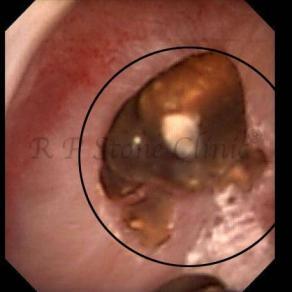

Kidney stone is a solid mass of CRYSTALS. It is the process of crystallization which initiates the formation of kidney stones. This happens in nephrons or units of kidney. Once a small crystal is formed, it can both grow & unite with other crystals leading to the formation of small concretion which eventually forms a stone. Once these large crystals detach from the collecting ducts, the process of stone formation starts in the renal collecting system. A recurrent kidney stone former is advised to know a little bit about something known as Randall’s plaque. Alexander Randall discovered plaques on the renal papillae eight decades back based on examination of 1154 pairs of autopsied Kidneys. He described these renal papillary lesions as cream colored or milk patch areas composed of calcium phosphate & calcium carbonate. These plaques could act as NIDUS for formation of KIDNEY STONE. Calcium Oxalate stone can form on this nidus & then detaches from this plaque to become a free floating stone in the collecting system of kidney

These images are taken as snap shots from the video recording of RIRS Surgery done at our hospital. These are Randall’s Plaques seen with Digital FLEX XC & Digital FLEX XC S. The cream or whitish patches are seen on the tips of RENAL PAPILLAE as seen in images below.

Randall’s Plaques may lead to the formation of Stones.

Those kidney stone patients who have Randall’s Plaques in their kidneys are more likely to form stones again (Recurrent Stones).

Stone Patients in whom Randall’s Plaques are detected at the time of RIRS Surgery should undergo regular ultrasound examination for early detection of stones.

Patients of Stones with Randall’s Plaques in their Kidneys should drink plenty of fluids in addition to Orange Juice & Lemonade.